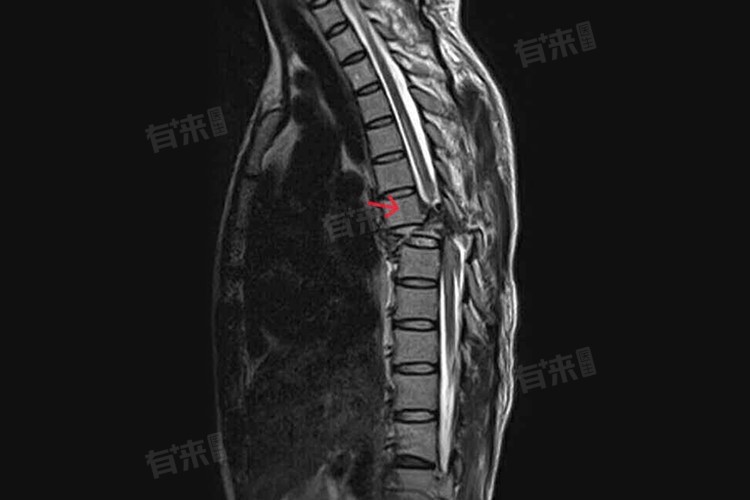

- 当胸椎间盘发生退行性改变后,纤维环可能破裂,髓核向外突出,压迫脊髓或神经根,引起疼痛、麻木等症状,胸椎核磁共振对软组织的分辨率高,能够准确显示椎间盘突出的部位、程度和方向,为手术治疗提供精准定位。

- 胸椎核磁共振的最大优势在于其能够显示胸椎及其椎管内的病变情况,如脊柱肿瘤、脊髓肿瘤、脊髓空洞症、血管畸形等,病变难以通过其他影像学检查手段发现。

- 而胸椎核磁共振能够清晰地显示病变的形态、大小和位置,为临床治疗提供重要信息。